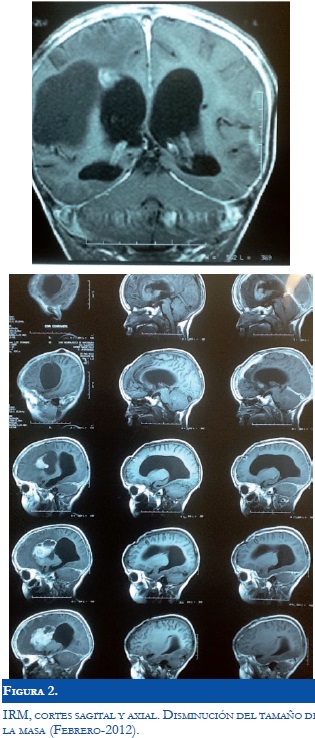

Ante la limitación para el manejo quirúrgico del Astrocitoma, se inicia manejo con Everolimus 2 mg/día. Durante la primera semana el paciente presenta mucositis oral, la cual mejora con manejo tópico. Dos semanas después el paciente permanece asintomático, por lo que se aumenta dosis de Everolimus a 2.5 mg/día. A los 4 meses de tratamiento, el paciente continua libre de crisis convulsivas, sin otros síntomas y sin efectos secundarios. El control de nivel sérico de Everolimus se encontró en 5 ng/ml. A los 8 meses presento convulsiones relacionadas con la suspensión del tratamiento antiepiléptico, que se controlaron fácilmente sin observarse deterioro clínico. En el control 1 año después del inicio del tratamiento (Figura 2), el niño continua sin presentar convulsiones y con mejoría de la movilidad del hemicuerpo izquierdo. En ese momento el paciente se encuentra escolarizado con adecuado aprendizaje y calidad de vida. En el último control, por aumento de peso y superficie corporal, se ajusta dosis de medicación a 5 mg/día y posteriormente, los niveles séricos se encuentran en 6.5 ng/ml.